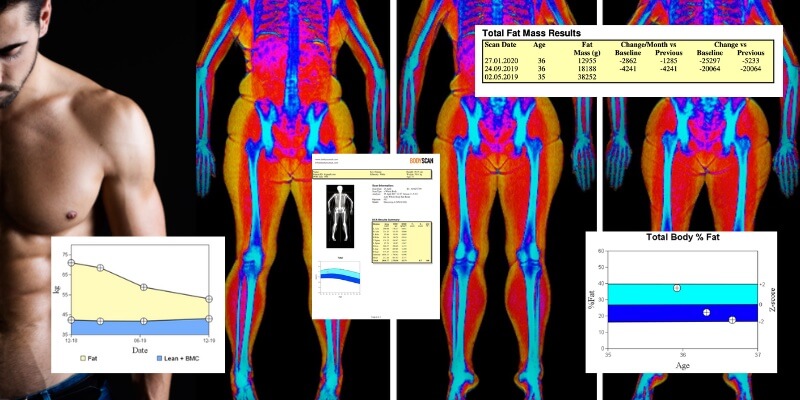

4. Absorciometría Dual de Rayos X (DEXA)

Este es el método más preciso para medir composición corporal, diferenciando entre masa magra, grasa y hueso, por lo que es ideal si buscas resultados detallados, aunque es costoso y menos accesible (dudo que alguien tenga un escáner DEXA en el baño).

Imagen 6: Análisis de un escáner DEXA.